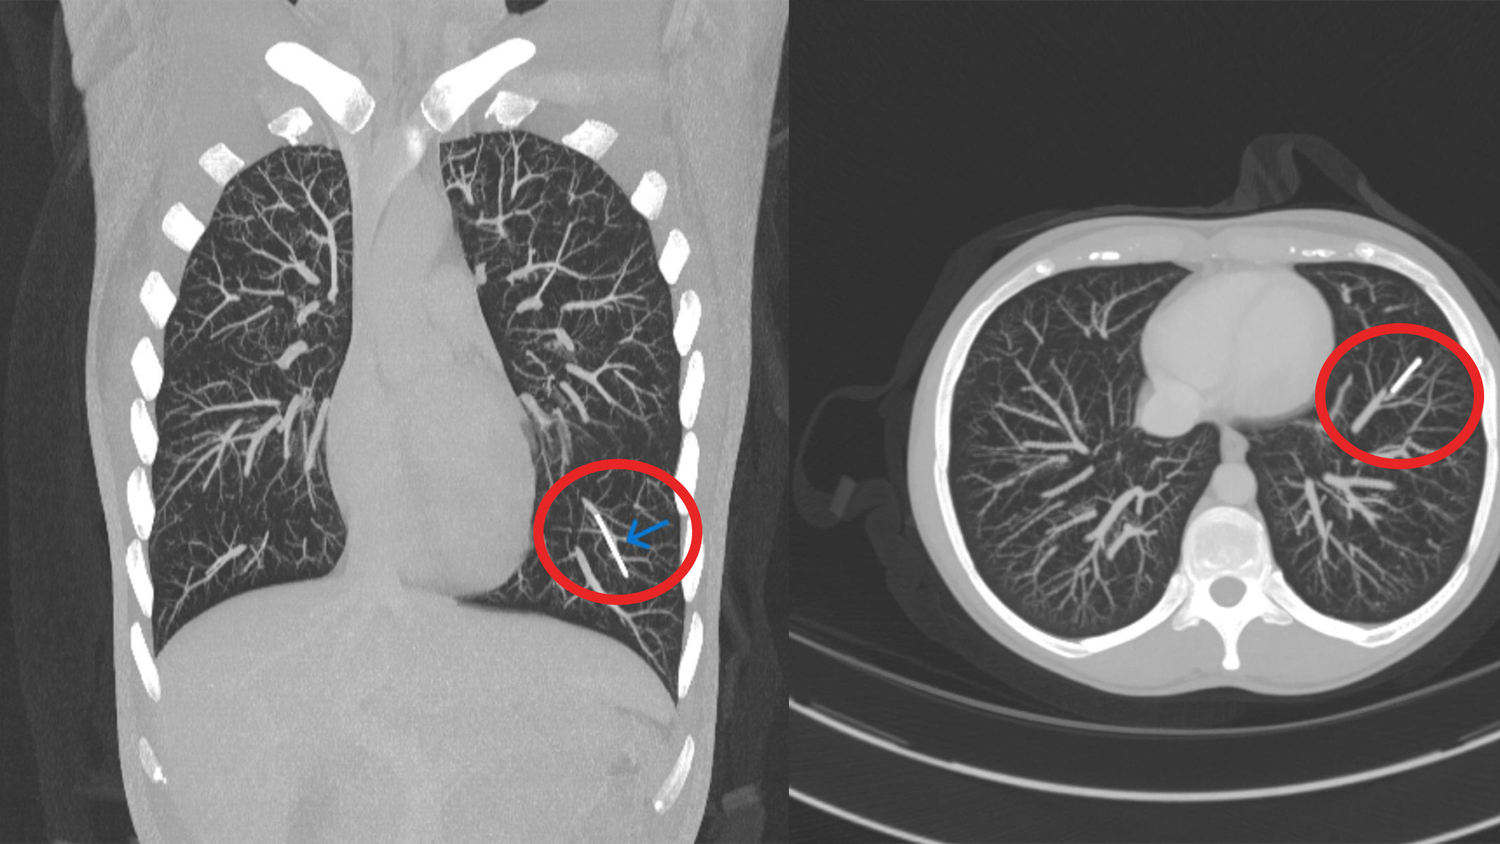

Das CT des Brustkorbs zeigte das Verhütungsimplantat im linken unteren Lungenlappen. Eine Entfernung des inzwischen verwachsenen Stäbchens würde nur im Rahmen einer teilweisen Lungenresektion möglich gewesen. Man hätte den betreffenden Lungenabschnitt entfernen müssen. Die Frau lehnte das ab, da sie keinerlei Beschwerden hatte. Also verblieb das Stäbchen in ihrer Lunge.